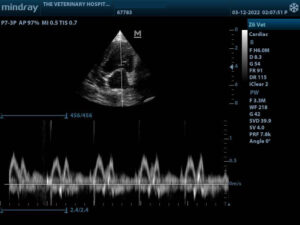

An ultrasound scan can show the size and shape of many organs and can also show abnormalities within them. An ultrasound scan is both painless and non-invasive and poses no risk of complications. Although ultrasound can be used to evaluate most soft tissues; the heart, abdominal organs and urinary bladder are the most frequently scanned in veterinary clinics.

Heart scan or Echo-cardiography is used to identify heart disease, the structure and function of the heart and its valves and for on-going optimal monitoring of the patient.